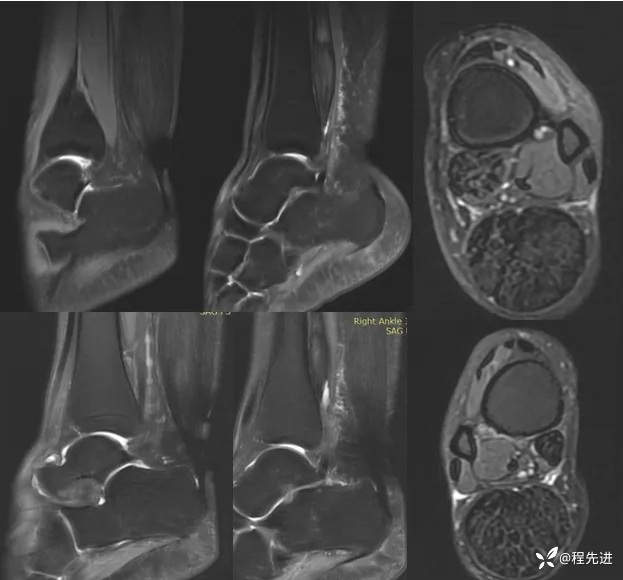

左、右踝关节MRI平扫: